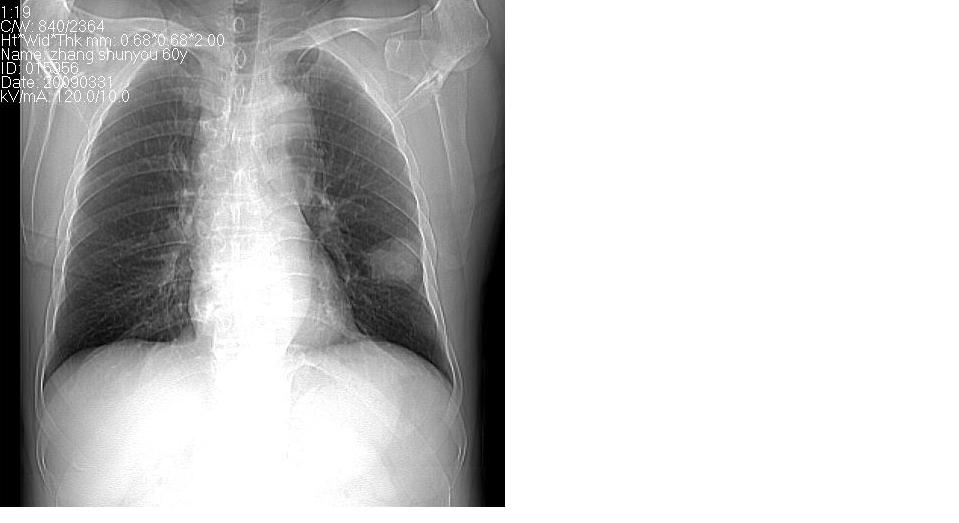

男 60岁,咳嗽,喀痰,胸闷,有吸烟史,正常图片未上传,请谅解。

考虑左肺下叶周围型肺癌可能性大。

分叶状肿块,有毛刺,有晕,有粗纹理直通肺门,支持考虑周围型肺癌